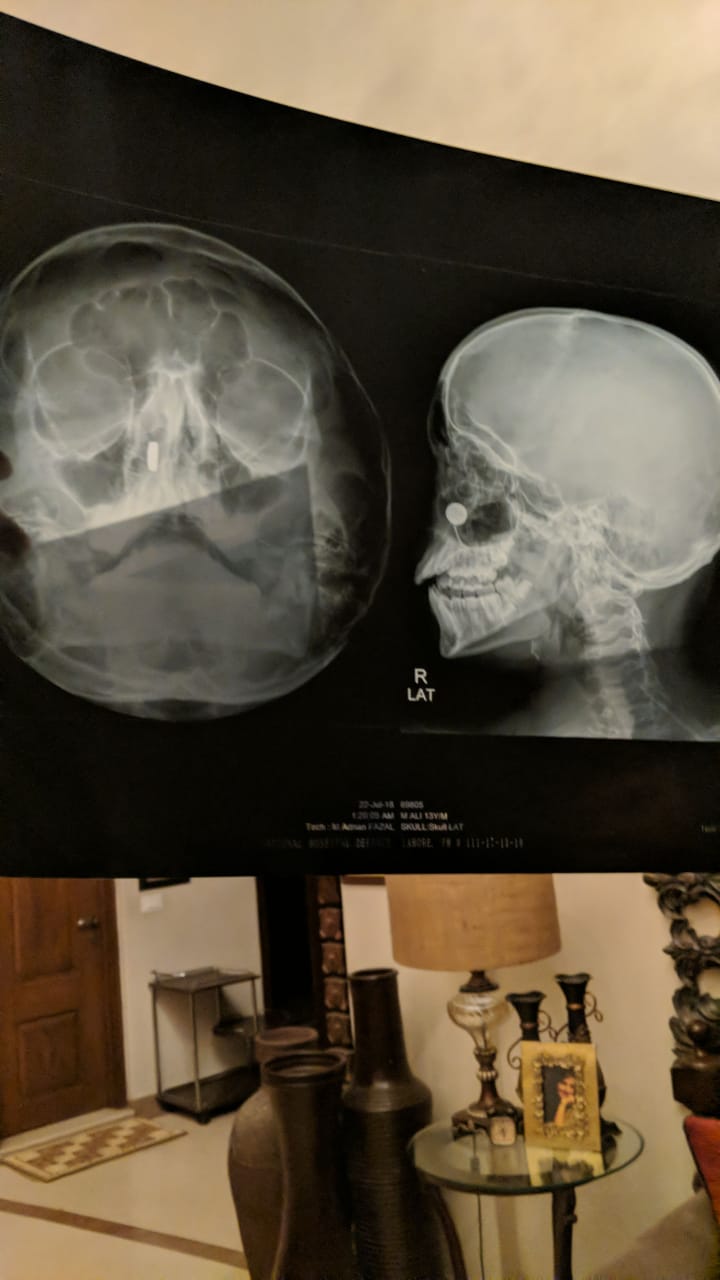

My 13 year old brother inhaled a button battery through his left nostril. Unable to find an ent at this time. Please suggest immediate course of action

Attach Photo here: